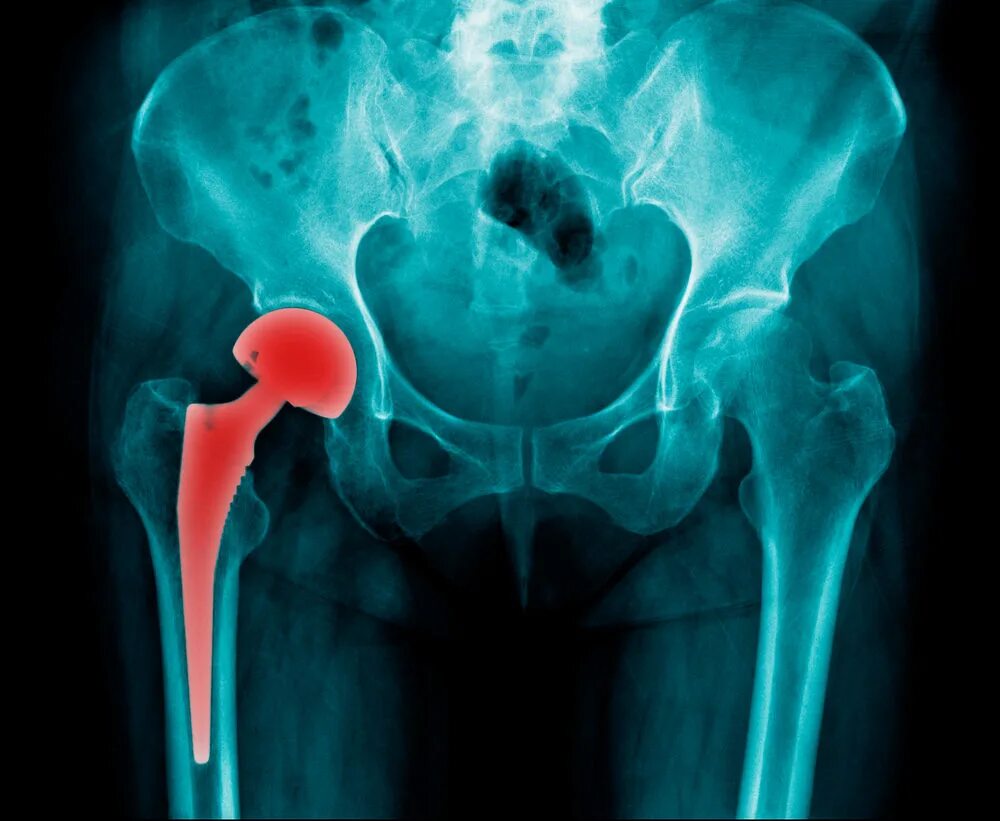

Перелом тазобедренного сустава в пожилом возрасте